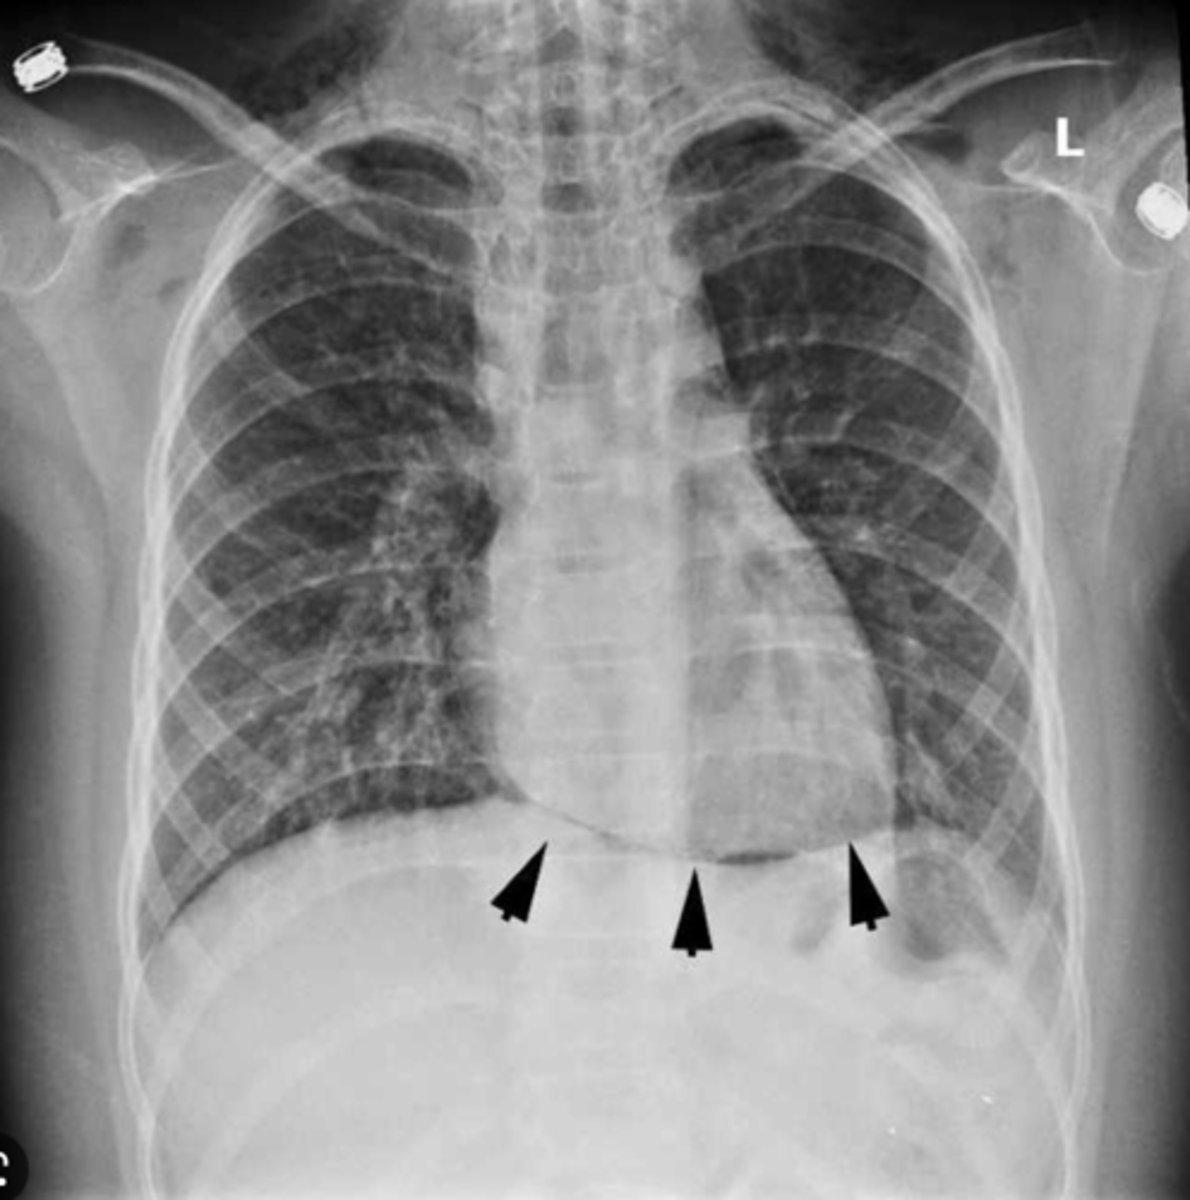

diaphragmatic surface of the heart

Formed by left and right ventricles. Sits on the diaphragm. Posterior view

inferior boarded of the heart

horizontal, formed mainly by right ventricle (on x-ray)